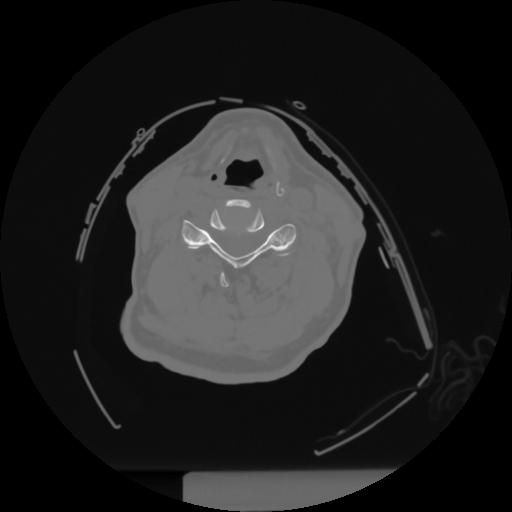

12 P.BLANDAS,,Vol,0.5,P.BLANDAS,,